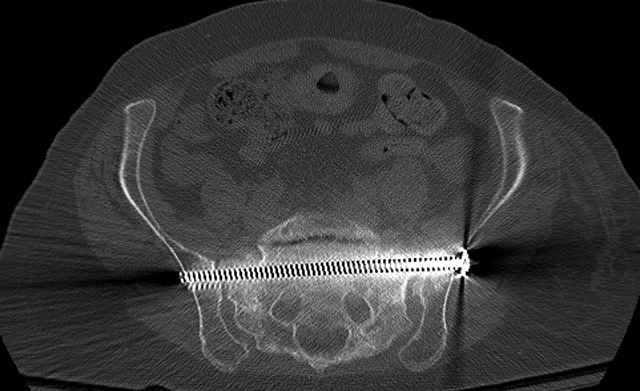

Here are a recent patient’s example slides...

54 yo Female Fell c/o Pain

Initial Films

?Instability on Exam - Limited by Pain

NonOp Initial Mgmt

3 Months After Fall

Continued Pain & Immobility

(+) Instability to Compressive Manual Exam

Pelvic CT Scan - 3 Months After Fall

Sacral Injuries

Ramus Fractures

Percutaneous Fixation

(B) Ramus-Retrograde

2 TransIliac-TransSacral

Upper Segment

mlcr